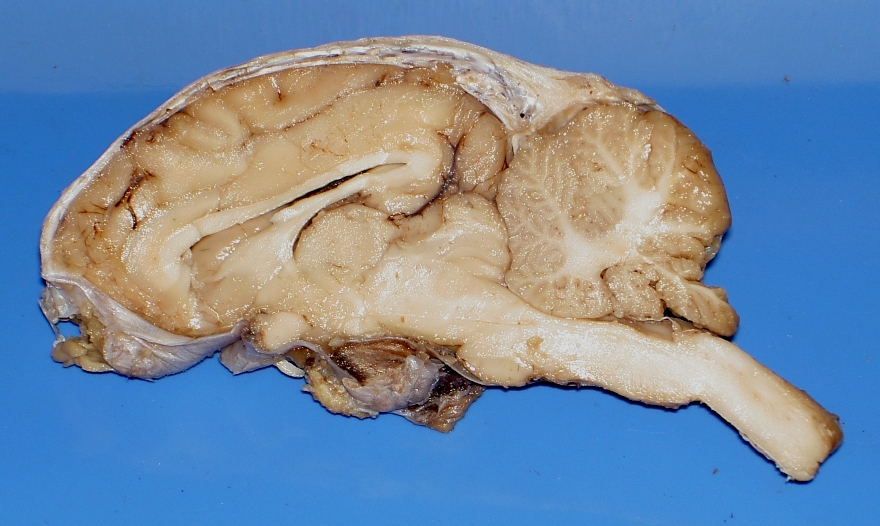

Images of Sheep Brains

These are unlabelled images of sheep brain dissections.

Use them to practice your identification of the listed structures.

2. coronal sections 1

7. sagittal section, R side